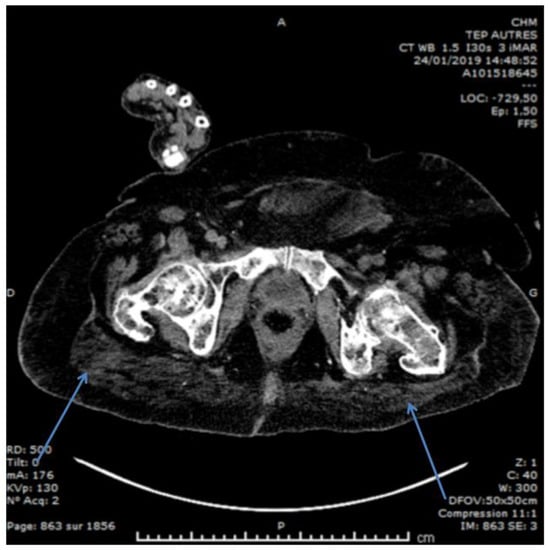

At present, the type of malnutrition most commonly encountered, at least in European settings, is sarcopenic obesity [81,82,83]. Although overweight or obese, patients present a severely reduced muscle mass, often with preserved calorie and protein intake (Figure 2). These cases are difficult to label; they are not malnourished in the usual sense, they do not have energy wasting, their BMI is normal, and their calorie intake is usually normal as well. Often, they do not have clear signs of malnutrition/PEW according to the standard parameters, such as prealbumin or transferrin levels, and their albumin levels may be modulated more by type of dialysis than by other means. Yet, they have a severely reduced muscle mass, and this reduction is correlated with survival [81,84,85,86,87].

Figure 2.

An example of sarcopenic obesity in a chronic hemodialysis patient affected by multiple myeloma. Arrows show poor quality, muscle tissue enrobed by well-developed adiposity.